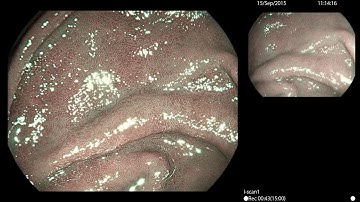

MagniView, i-scan and i-scan OE in Barrett´s associated dysplasia - UGI